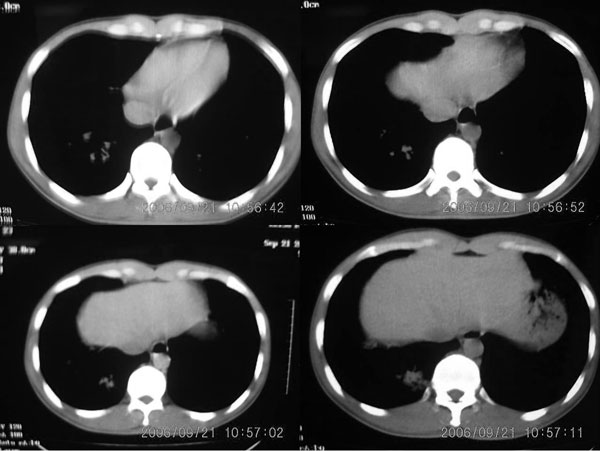

右肺门影增大,纵隔内可见多个淋巴结肿大,右肺下叶内后基底段斑片状模糊影,两肺间质性改变;考虑右肺内结核并右肺门及纵隔淋巴结结核可能性大;职业病及结节病待排;肿瘤不太支持,年龄轻,无咯血,未见明显支气管狭窄,建议穿刺活检。

m 27 右肺门影增大,纵隔内可见多个淋巴结肿大,右肺下叶内后基底段斑片状模糊影,两肺间质性改变;考虑结节病或结核,建议纤维支气管镜穿刺活检.鉴别诊断1;淋巴瘤,纵隔淋巴肿大(胸骨后淋巴肿大突出)进展快,范围不够大,无融合及包埋改变..2结核其淋巴结密度是不均匀的,其内部一般有干酪坏死.可有钙化.可做ppd试验进一步明确.3结节病往往表现为肺门淋巴结对称性肿大.

右肺下叶后基底段结节样病灶,边界不规则,密度不均,右肺门团片影,肺门增大,纵隔见肿大淋巴结.结合临床首先考虑:肺结核。淋巴瘤待排

补充一点,患者体检近期有双侧颈部淋巴结肿大

右肺下叶后基底段结节样病灶,边界不规则,密度不均,右肺门团片影,肺门增大,纵隔见肿大淋巴结.

考虑1、纵隔及肺部淋巴瘤.2、结节病